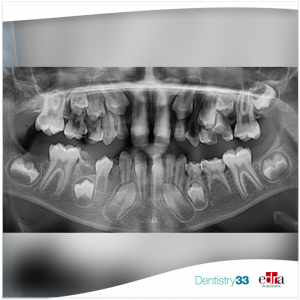

A 19-year-old patient presented a bilateral posterior dental open bite with lingual interposition during swallowing that was not resolved with a previous fouryears orthodontic treatment with fixed appliance.

The diagnostic hypothesis of Primary Failure of Eruption emerged, so a genetic analysis with molecular analysis of the PTH1R gene was required. The analysis showed heterozygosity in the sequence variant c.322-322deIT (p.C108Vfs*82), that is associated with Primary Failure of Eruption. This finding confirmed the diagnosis of Primary Failure of Eruption.

As in patients with Primary Failure of Eruption an orthodontic treatment with teeth extrusion can cause their ankylosis, in the case presented it emerged the hypothesis that the previous orthodontic treatment might have promoted this process and that, therefore, it could have been performed because Primary Failure of Eruption has probably not have been suspected at the time of treatment begin.

By considering the patient’s age, the level of infraocclusion and posterior open bite, and by suspecting the dental ankylosis of the infraoccluded teeth, the clinicians decided to refer the patient to a maxillofacial surgeon for the evaluation of the most appropriate therapeutic option for the management of the case.

Primary Failure of Eruption should be suspected if a bilateral infraocclusion or ankylosis of the teeth causing open bite is present, in order to avoid an orthodontic treatment which could lead to dental ankylosis.